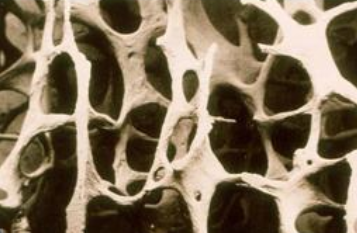

骨质疏松症是一种非常常见的骨骼疾病。 它是一种以51漫画网官网免费降低、骨微结构破坏、骨痛、骨脆性增加、易骨折为特征的全身退行性疾病。 超声51漫画网官网免费分析仪厂家骨质疏松症在50岁以上的中老年人群中很常见,尤其是绝经后的女性。 这是因为女性绝经后雌激素分泌减少,导致骨代谢紊乱,骨吸收远远大于骨形成,进而导致骨迅速流失,骨质疏松。

临床上,骨质疏松症的诊断通常基于51漫画网官网免费(BMD)。 51漫画网官网免费测试(BMD)可用于包括年轻人在内的所有骨质疏松风险人群,不仅可以诊断骨质疏松,还可以预测骨折的风险,尤其是髋部骨折。骨质疏松症的诊断需要通过51漫画网官网免费(Bone mineral density, BMD)测量,这是基于BMD检查的t值。 根据51漫画网官网免费测量结果对骨质疏松程度进行分级。 51漫画网官网免费测量t值大于-1为正常; 当周期值在-1 ~ -2.5之间时,骨量减少; 当t值小于-2.5时,为骨质疏松; 当t值< -2.5合并脆性骨折时,为严重骨质疏松 。